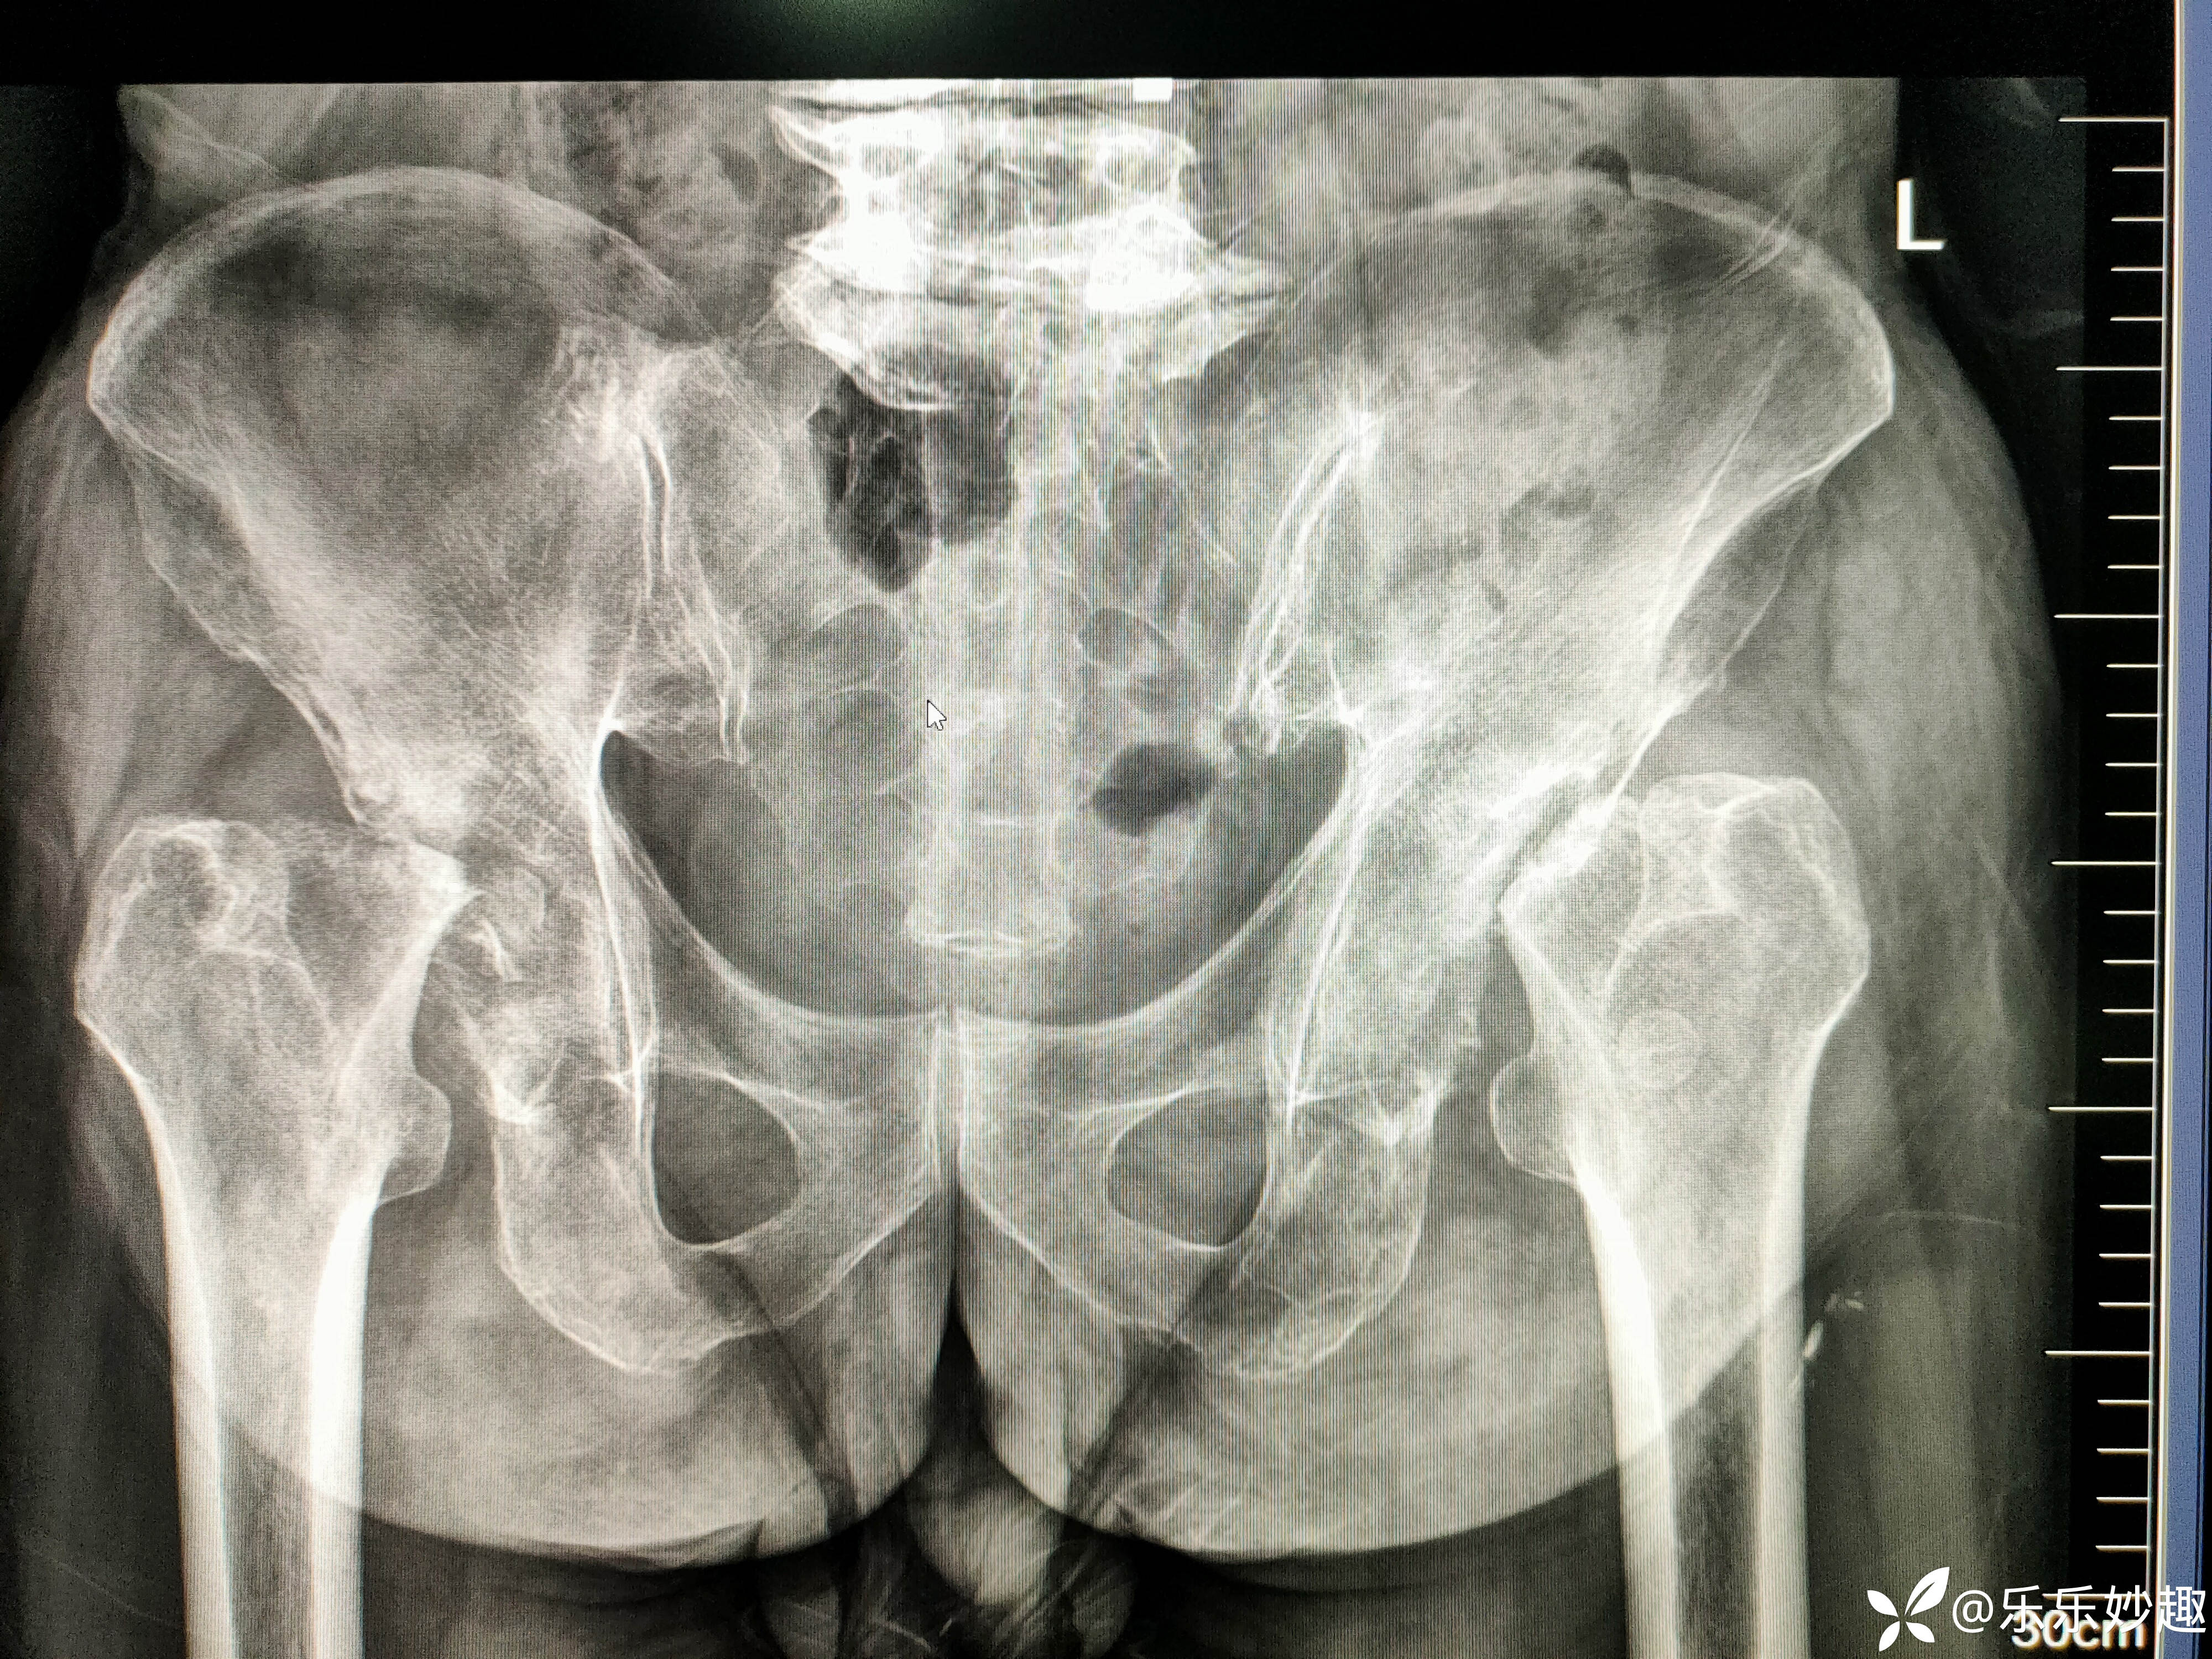

2024年9月拍了骨盆DR片,见下图